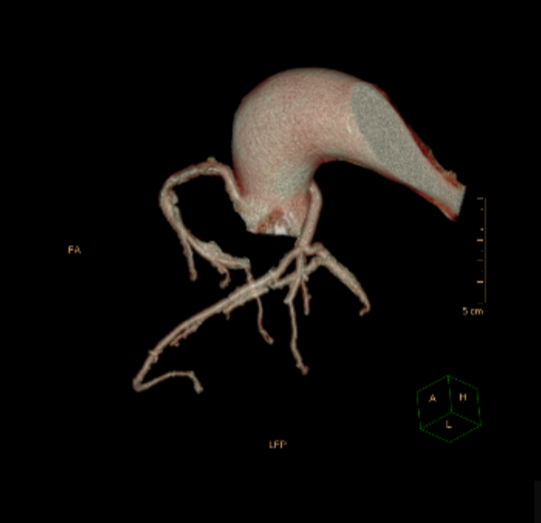

经快速测量患者为Type1 R-N融合二叶瓣,超声测量瓣环内径20mm,CT测量瓣环内径25.9mm

术中影像

左侧股入路建立体外循环通路

右侧入路造影评估入路条件 血管无明显迂曲,内径偏细

根部造影

可见大量反流 横位心 升主扩张